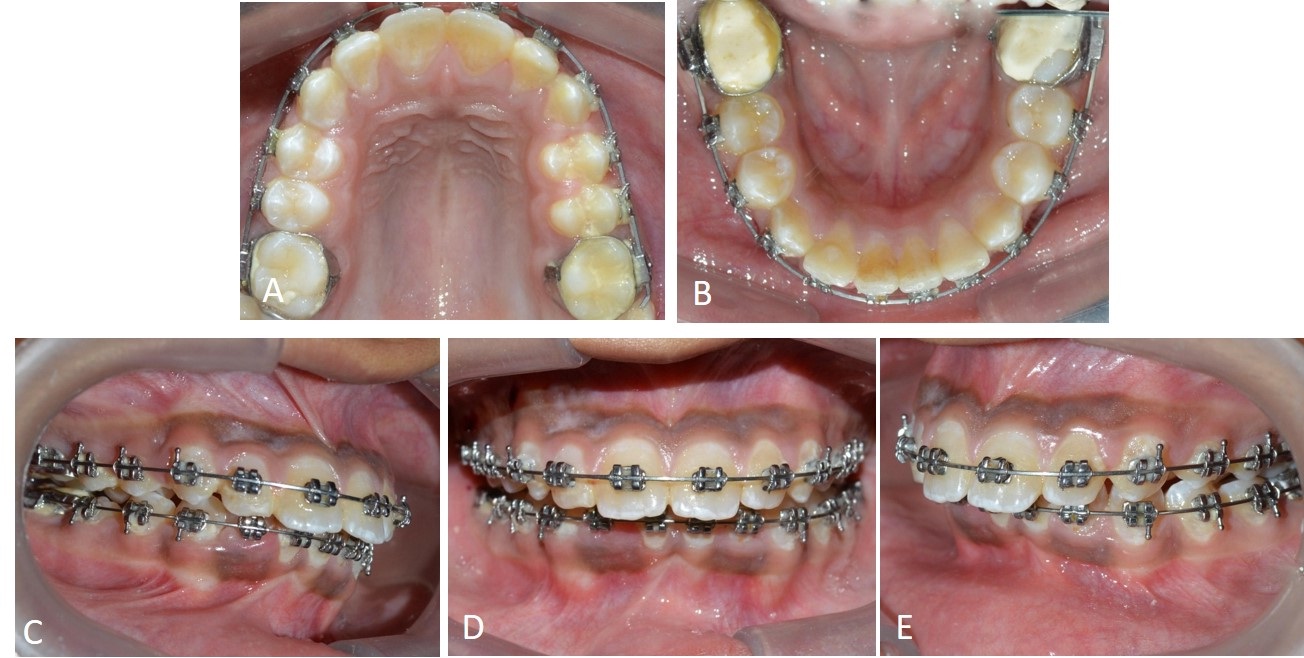

A 22-year-old female presented with chief complaint of malalinged upper front teeth. On extraoral examination patient had straight profile and competent lips, intraoral examination revealed Class I molar relation bilaterally. Upper right and left canines (teeth #13,23) were palatally placed [Table/Fig-4].

Non-extraction treatment was planned for the patient since sufficient space was present between the upper right and left lateral incisors and first premolars for alignment of canines. Initial alignment was started with 0.016” NiTi wire. Maxillary canines were not bonded initially. After reaching 0.018” SS wire, Begg’s auxiliary bracket was bonded on maxillary canines palatally. The upper arch was consolidated into two posterior and one anterior segment and power chain was placed from upper right first permanent molar to upper left first permanent molar engaging the auxiliary bracket on canines forming slings around the canines [Table/Fig-5]. Re-activation of power chain was done after three weeks and (teeth #13,23) were brought into line of arch in six weeks [Table/Fig-6].

Pretreatment intraoral photographs showing bilaterally palatally placed canines (in crossbite) in upper arch.

Power chain placed for alignment after reaching 0.018” stainless steel wire in a slingshot technique.

Post alignment intraoral photographs of bilaterally palatally placed canines in upper arch.